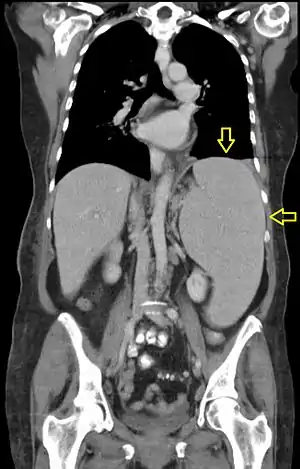

| CT scan in a patient with chronic lymphocytic leukemia, showing splenomegaly. Yellow arrows point at the spleen. | |

Computed tomography shows a massively enlarged spleen ( splenomegaly).